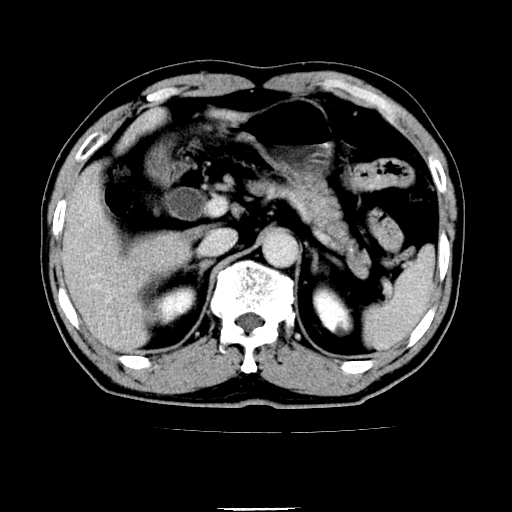

以下是引用chenqiong在2010-3-25 20:56:00的发言:[br]1、胆囊炎,胆囊息肉[br]2、肝内胆管及胆总管扩张,胆总管下端结石[br]3、十二指肠乳头旁憩室

以下是引用zxl51642在2010-3-26 10:47:00的发言:[br]胆囊炎,胆囊息肉,胆总管扩张,但未看到明显肿块,肝内胆管扩张不像恶性,炎性狭窄或阴性结石可能吧,建议mrcp,右肾小囊肿